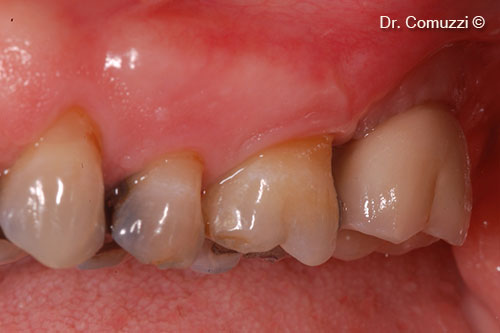

11. Case completed with 27 in place

12. Follow-up at 3 years

13. Follow-up at 4 years

14. Follow-up at 12 years